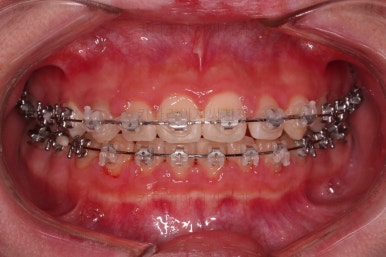

틈이 다 모였고 교합도 많이 좋아졌죠?

끝내도 될까요?

전후 사진을 비교해 볼게요.

악궁확장을 통해 위아래 악궁의 크기 조화를 맞췄고, 틈새도 모았으며 교합도 적절히 마무리를 했습니다.